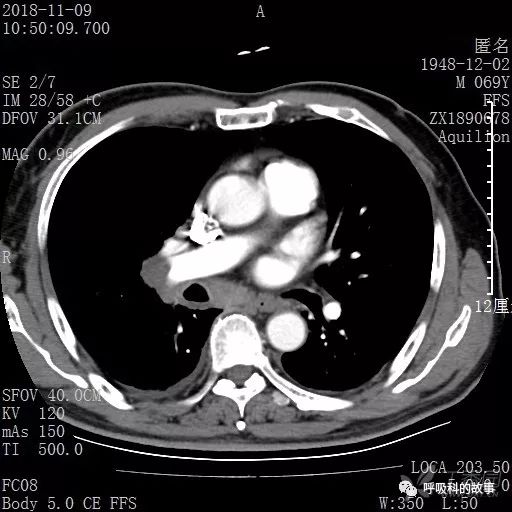

胸部增强CT示右肺门占位伴远端阻塞性肺炎,纵膈、右肺门、右侧颈根部、右侧腋下及肝门部肿大淋巴结。两侧胸腔少量积液。

肺窗CT